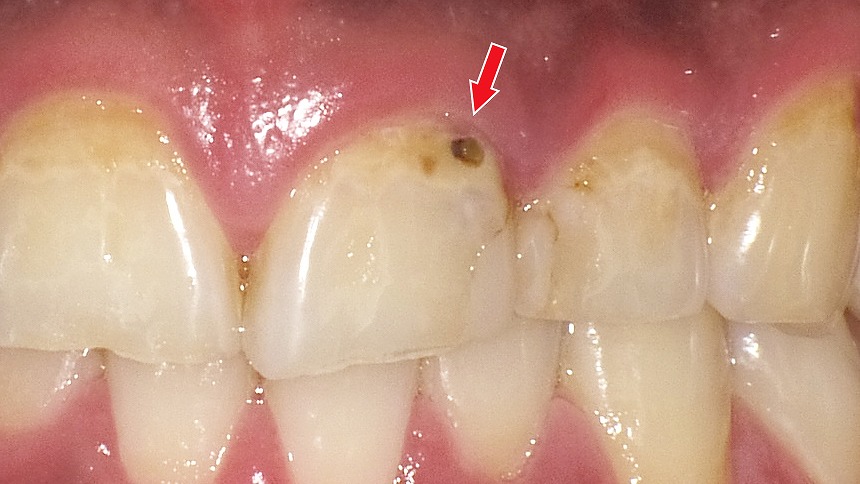

初期虫歯(C1)は、虫歯がエナメル質の内部まで進行し始めた段階を指します。まだ穴は大きく開いておらず、痛みやしみる症状が出ないため、自覚しにくいのが特徴です。見た目としては、黒い点や小さな溝の変色として確認されることが多く、歯科医師による診断が重要になります。

赤矢印が示すように、歯と歯の間(コンタクト部)の初期虫歯は、肉眼ではほとんど確認できません。レントゲンを撮影することで、エナメル質内部の透過像として虫歯を早期に発見できます。見た目に穴がなくても進行している場合があるため、定期的なレントゲン検査は非常に有効です。